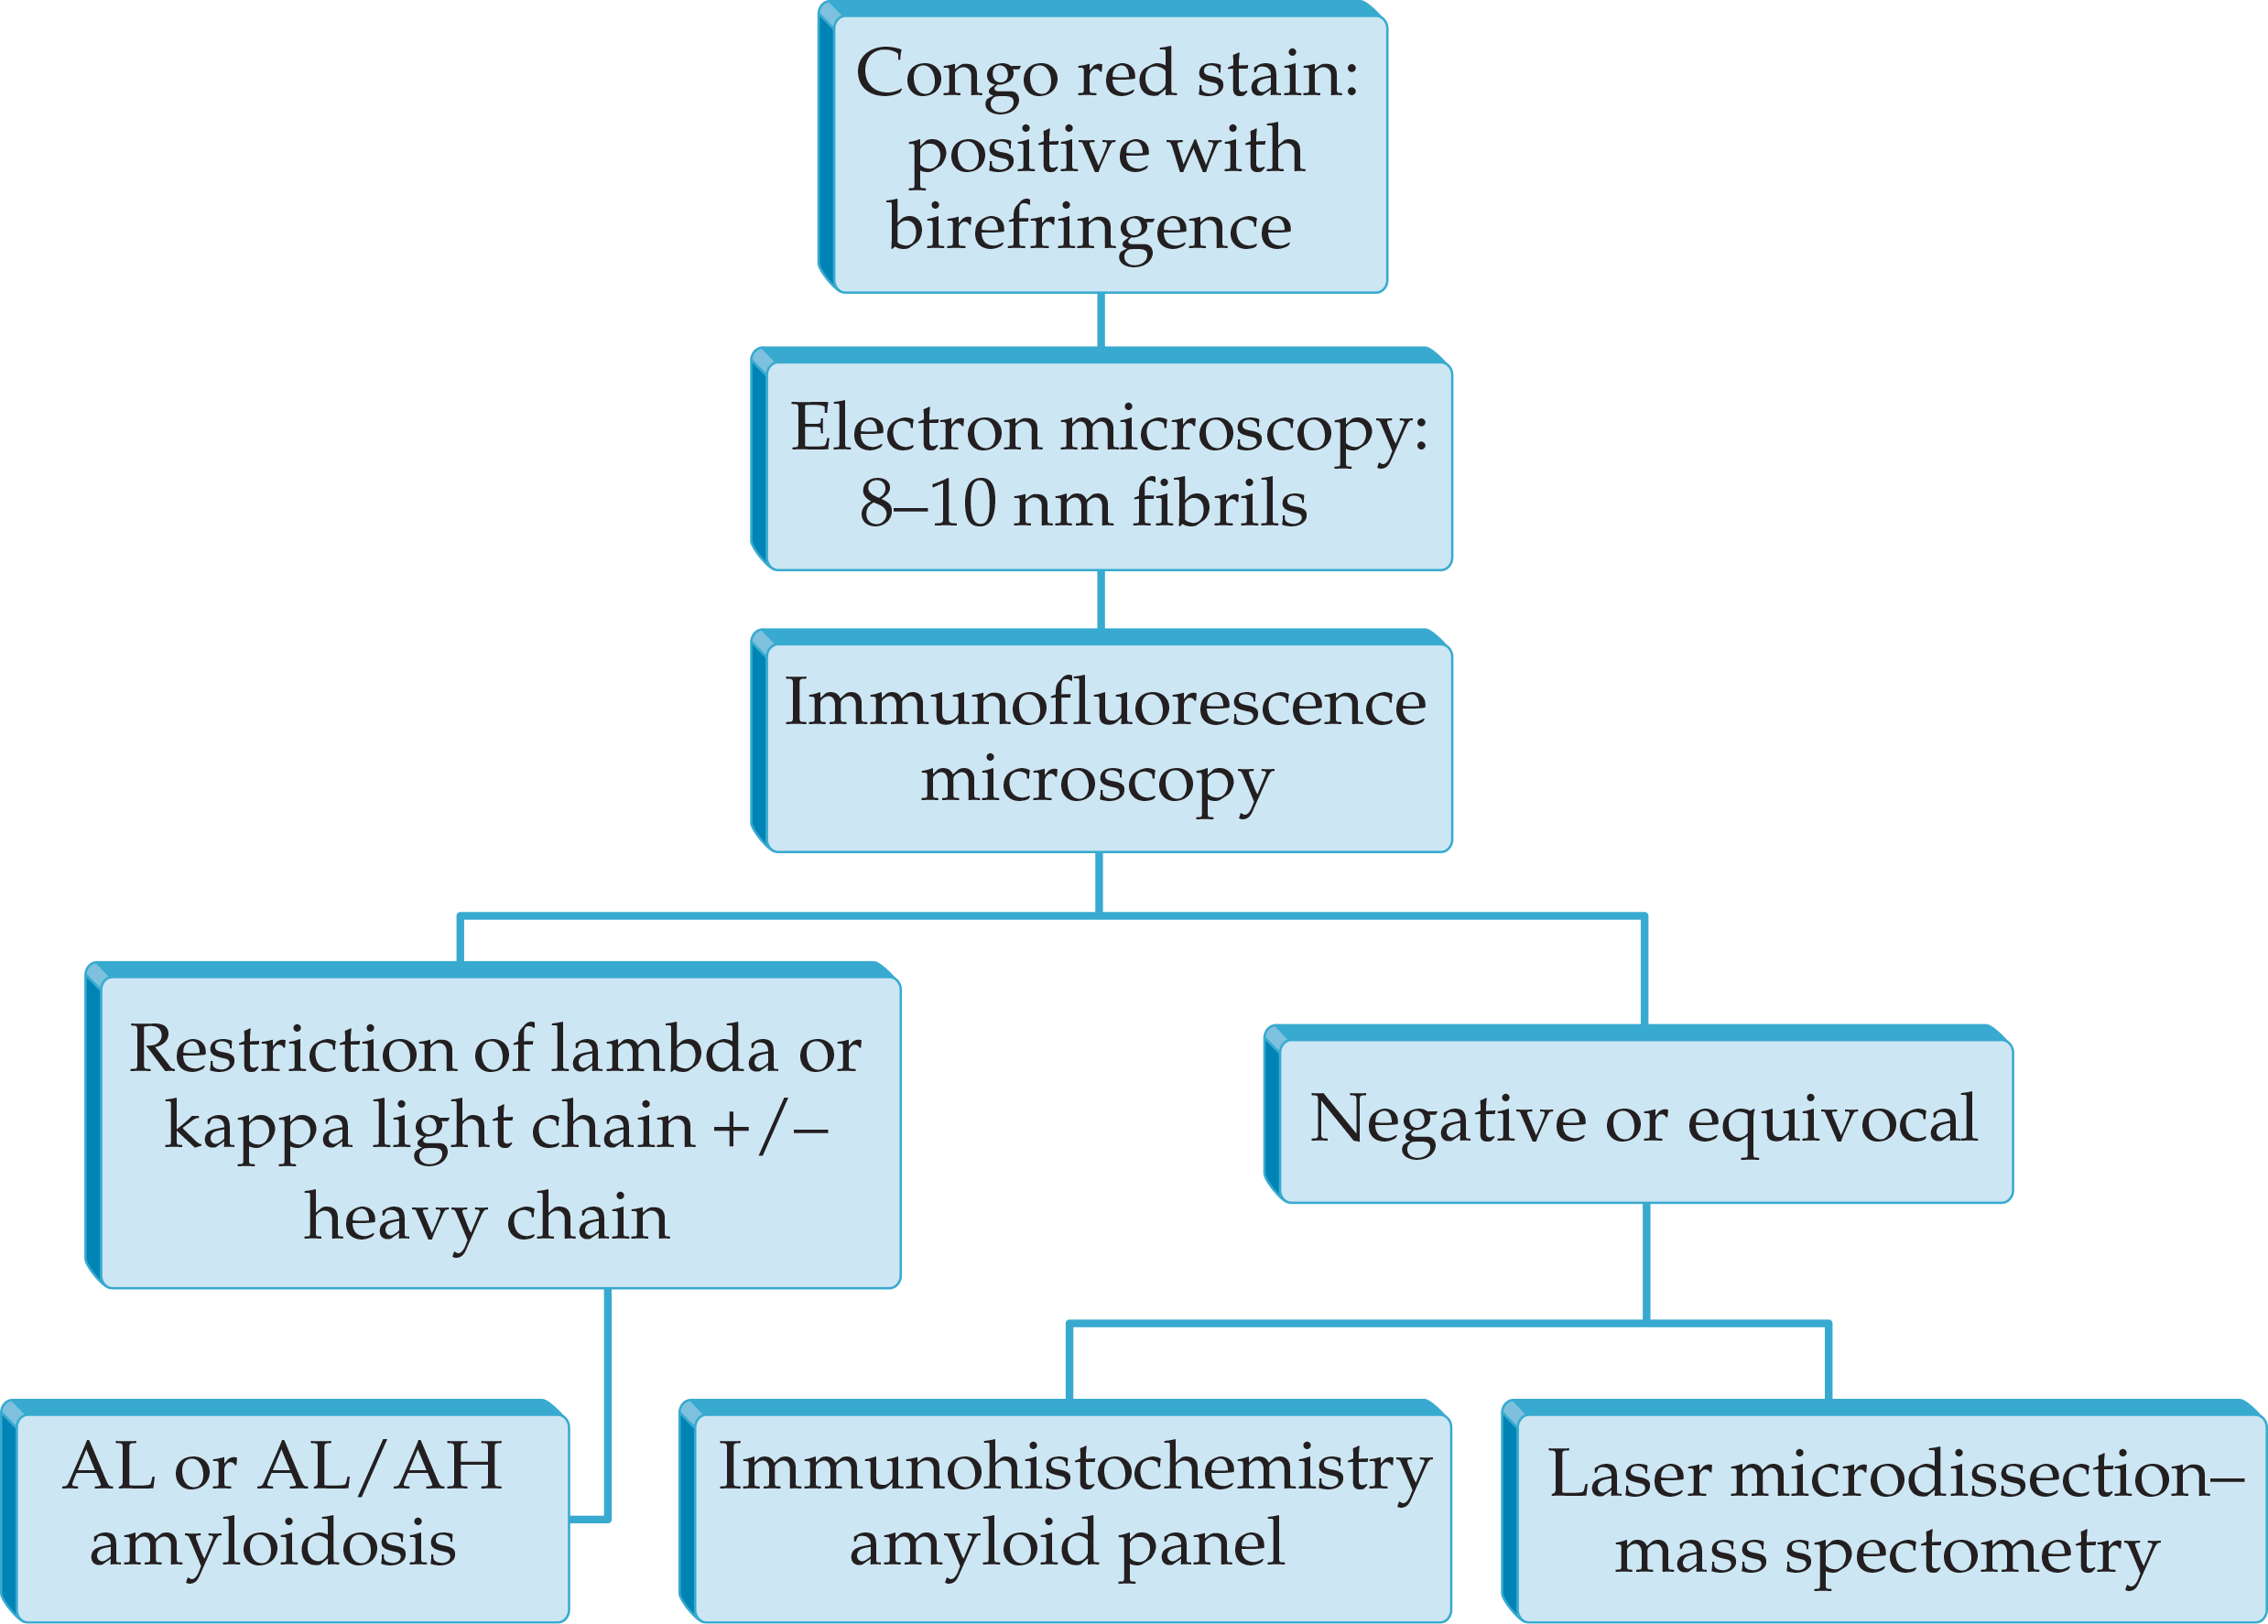

- Best practice for typing of amyloidosis